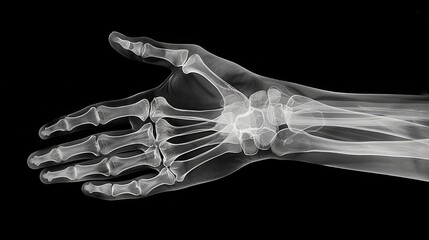

画像検査

エコーやレントゲンなどの画像検査は、関節の滑膜の腫れや、骨びらんなどの変化を確認するために行われます。リウマチは初期段階ではレントゲンで異常が見られないことがありますが、超音波やMMPなどの製剤を用いた検査でより詳細な状態を把握することが可能です。これにより、治療の効果や進行状況をモニタリングし、適切な療法を行います。

- レントゲン:レントゲン検査は、リウマチが進行すると関節や周辺組織に変化が現れるために行われます。これにより、関節の破壊や骨の変形などの異常が可視化されます。しかし、レントゲンは早期の段階での変化を捉えるのは難しいため、リウマチの初期診断には限界があります。通常、他の検査と併用して使用されます。

- 超音波検査:超音波検査は、関節や組織の炎症を詳細に観察するために使用されます。特に早期のリウマチの症状を捉えるのに有用であり、関節の内部構造や炎症の程度を評価します。超音波はリウマチの早期診断において非常に有力なツールとされています。

Q3. レントゲンと超音波検査の違いは何ですか?

レントゲンは骨の変化を評価し、超音波検査は関節や組織の炎症を観察します。超音波は関節の内部構造や炎症の程度を評価するのに優れており、関節リウマチの早期段階の変化を詳細に捉えることが可能です。